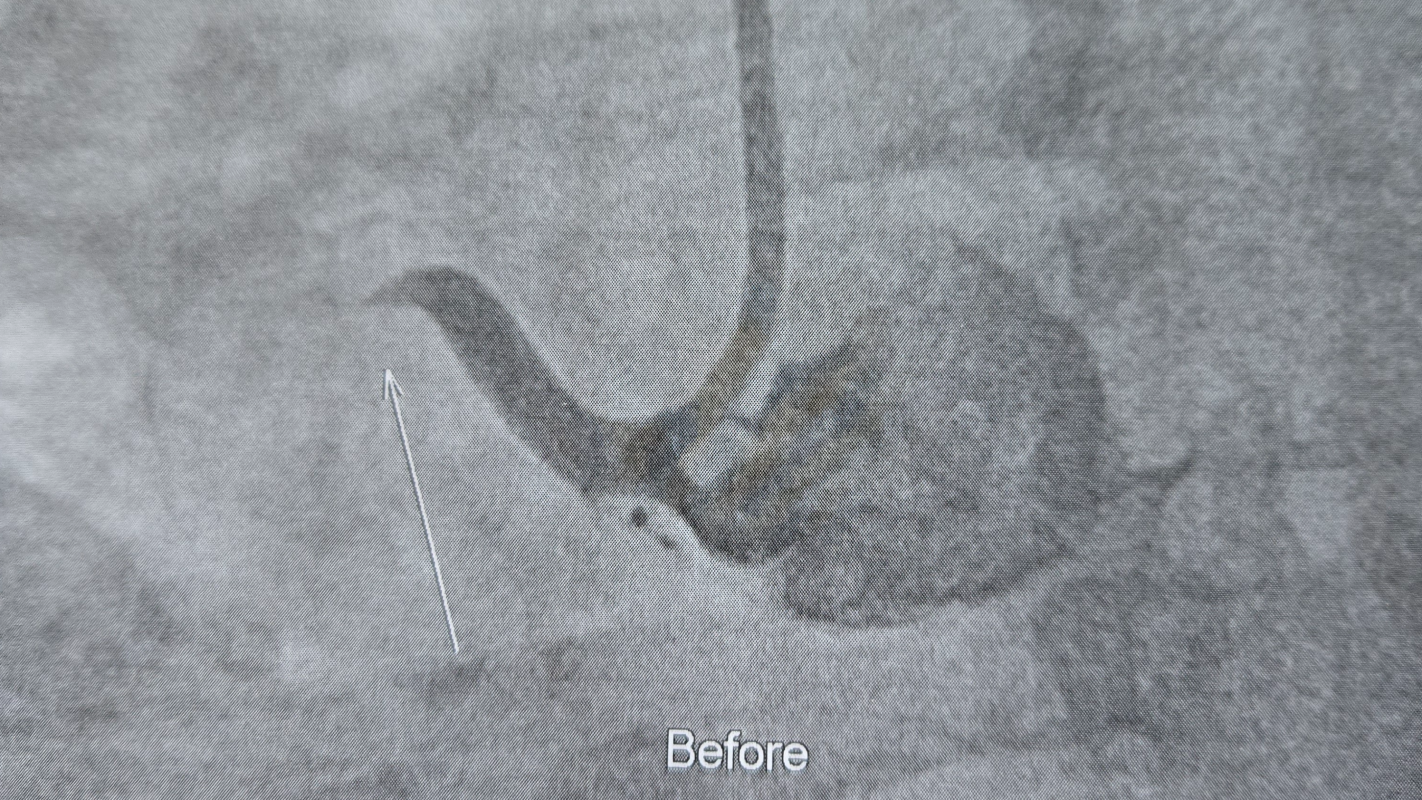

We are having financial problems since my heart attack.the bills arent getting paid.we have no food.i havent gotten a paycheck in 2 months and still at home due to complications of my procedure.